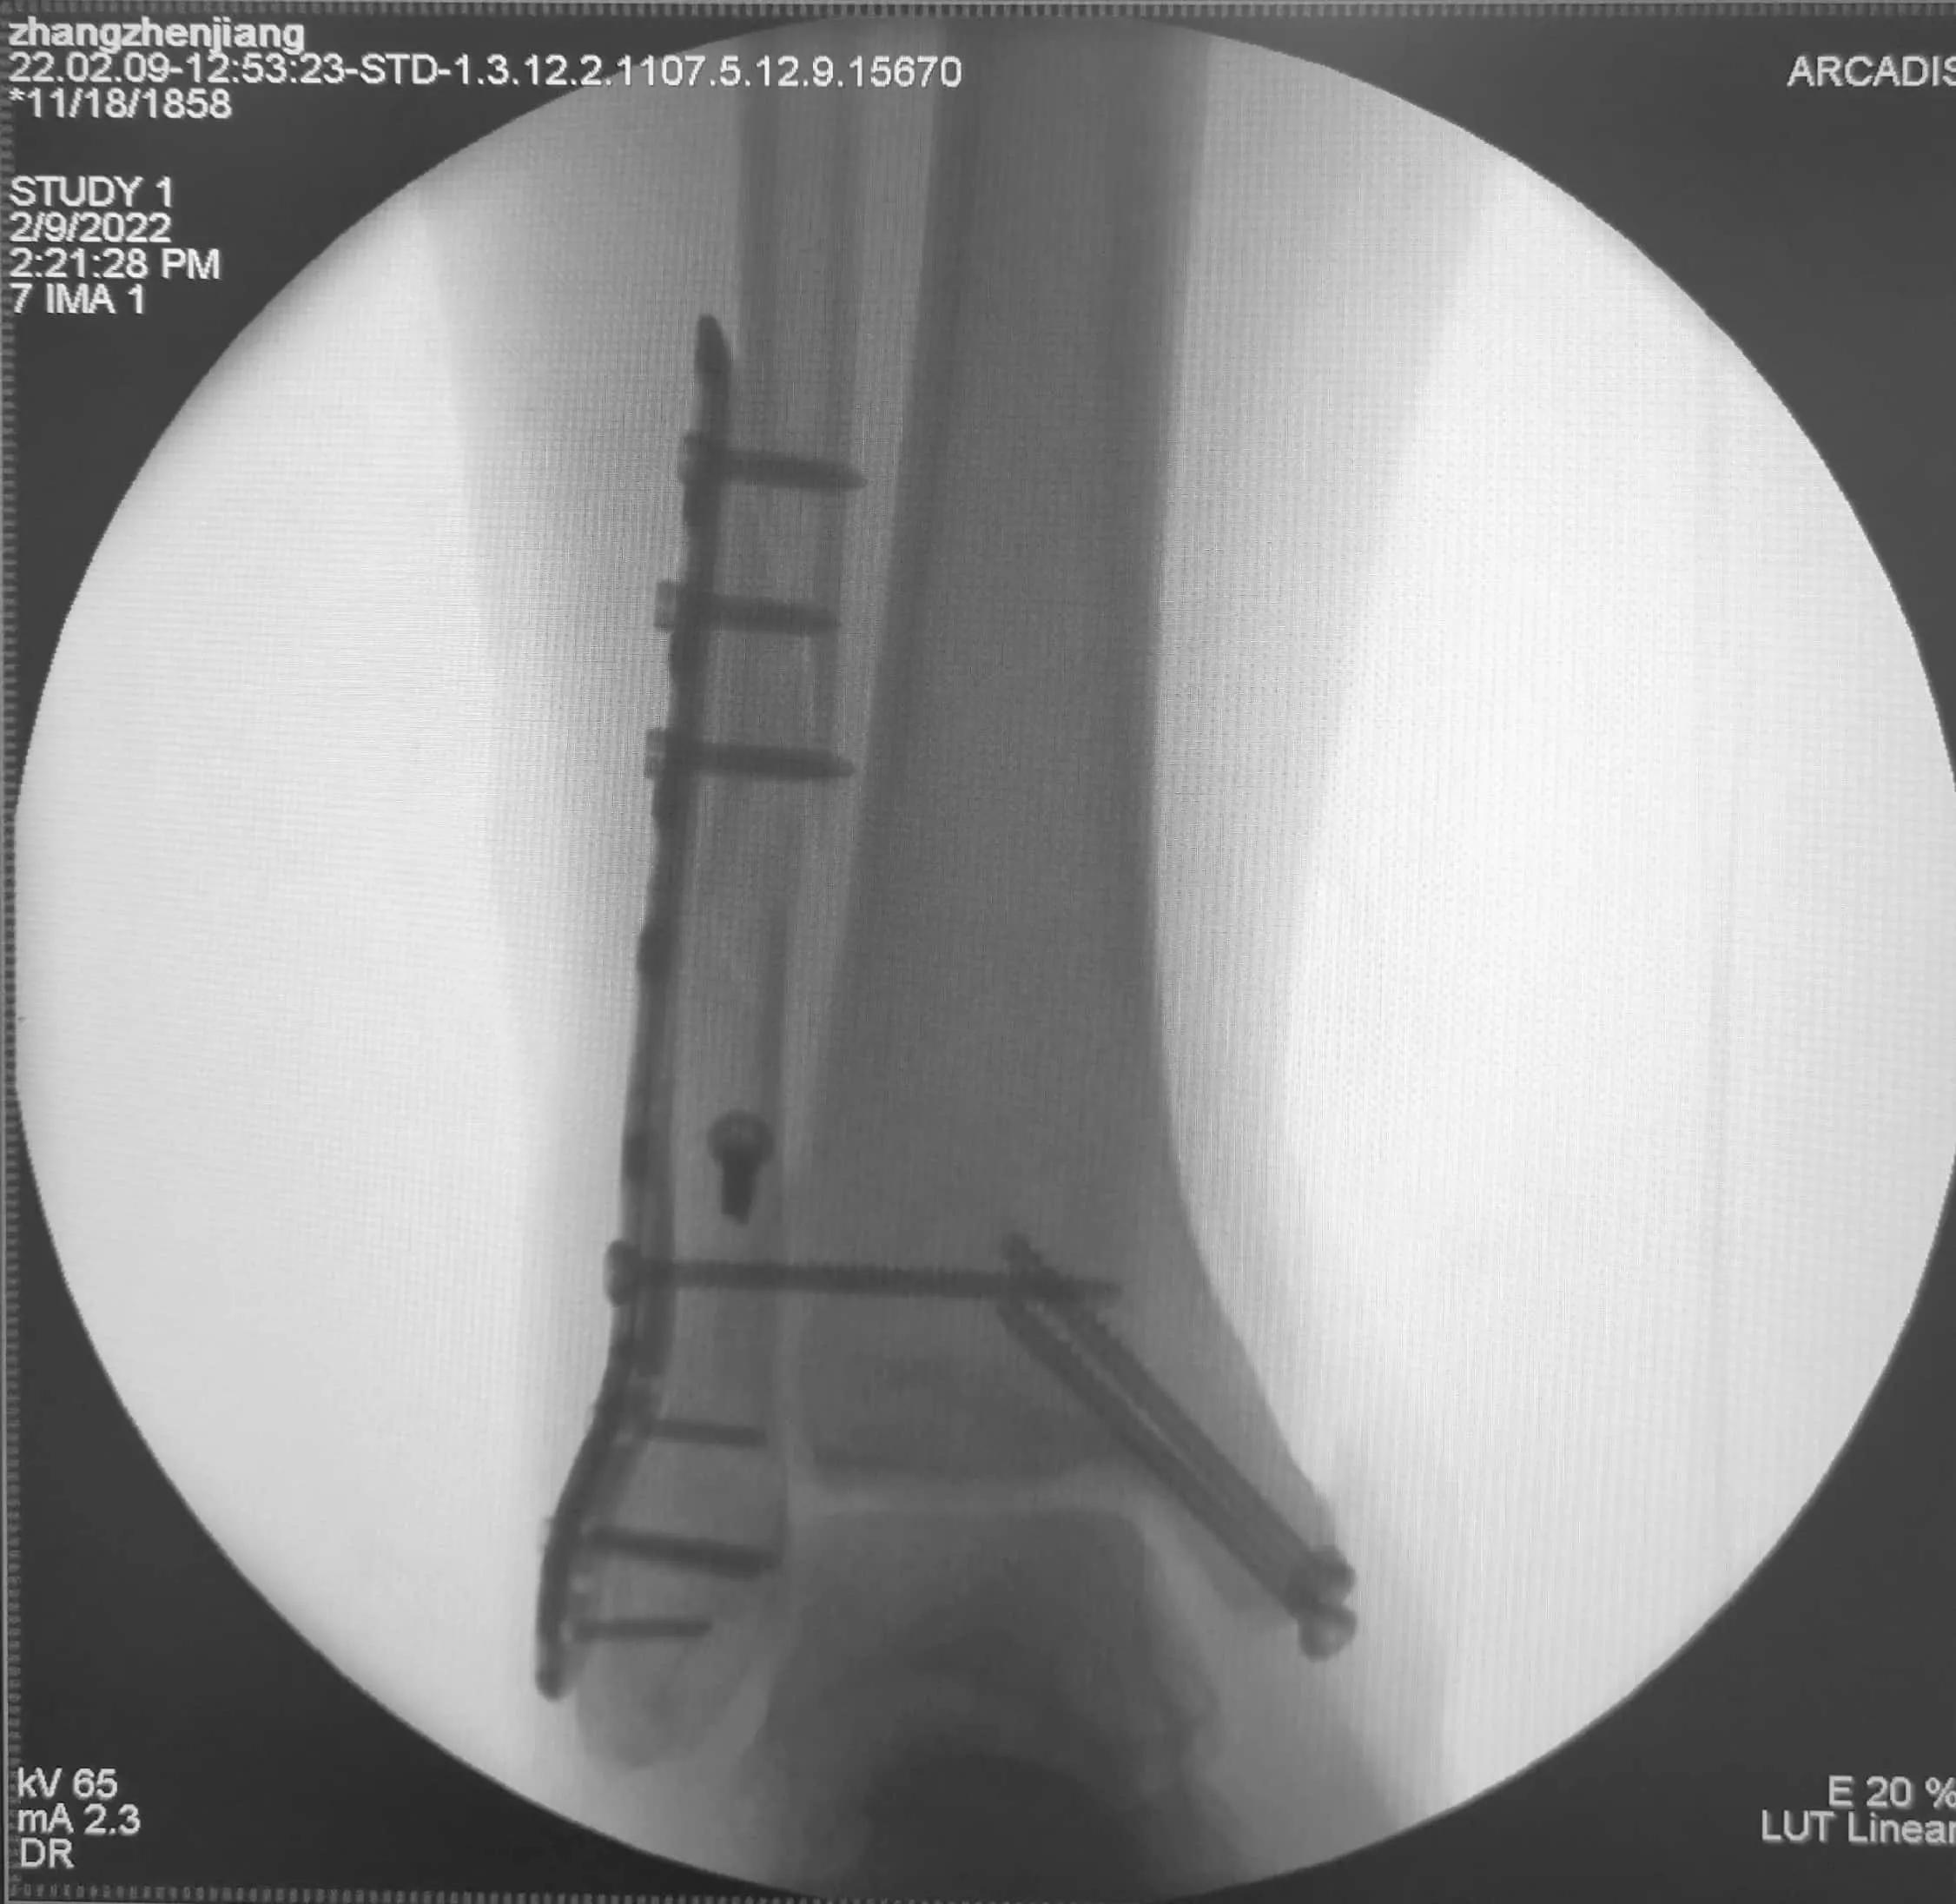

2022年2月9日手术中照片

幸运的是,今天手术踝关节骨折获得了满意的复位!